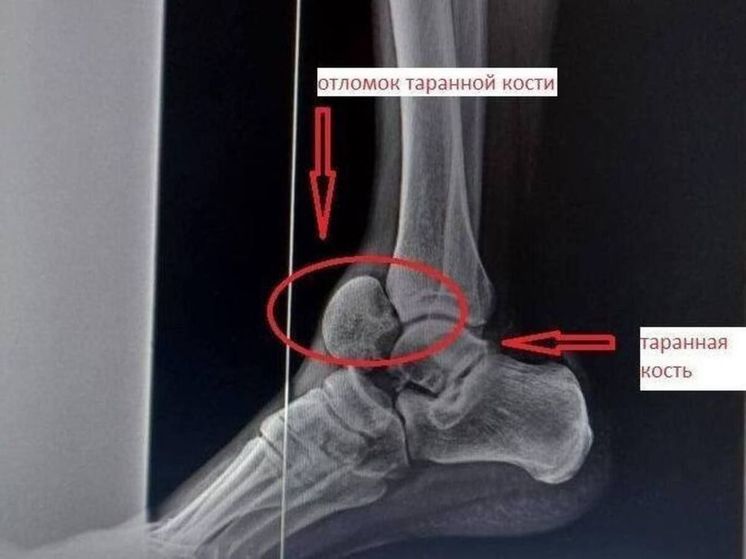

Фото: Министерство здравоохранения Московской области

В результате обследования медики обнаружили травму таранной кости. Ее перелом считается редким. Лечение возможно было только с помощью операции. Костный отломок врачи вернули на место. Части кости зафиксировали винтами.